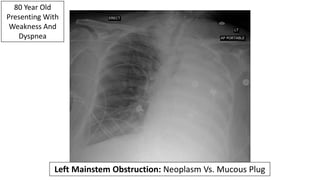

80 Year Old

Presenting With

Weakness And

Dyspnea

Left Mainstem Obstruction: Neoplasm Vs. Mucous Plug

Bronchoscopy Reveal A Mucous Plug